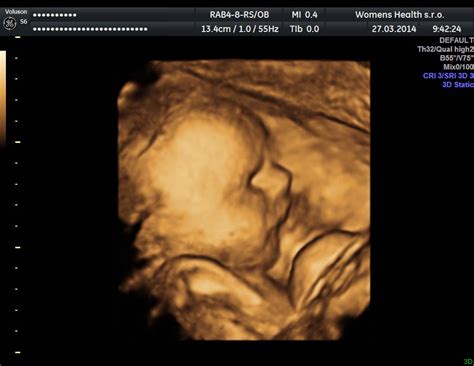

V 12. týždni tehotenstva vás čaká prvý trimestrálny skríning, ktorý zahŕňa ultrazvukové vyšetrenie a krvné testy (PAPP A test). Tieto vyšetrenia pomáhajú odhaliť možné vrodené chyby plodu. Na ultrazvuku uvidíte svoje dieťatko, ako sa pohybuje a kopká.

12 Week Pregnant Ultrasound | Plus First Trimester Screening and Symptoms.